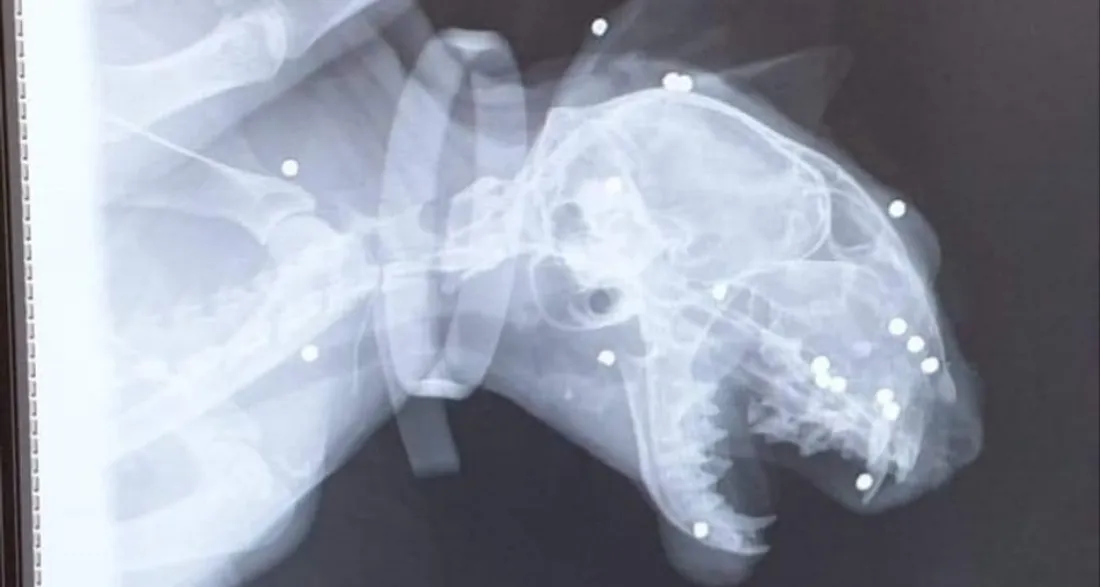

Péronne : condamnation du tireur de 18 plombs dans la tête d'un chat

L'animal est devenu aveugle et a terriblement souffert suite à chacun de ces impacts.

Ce jour d'avril dernier, elle avait reçu 18 plombs dans la tête simplement parce qu’il s’était rendu dans le jardin du voisin.